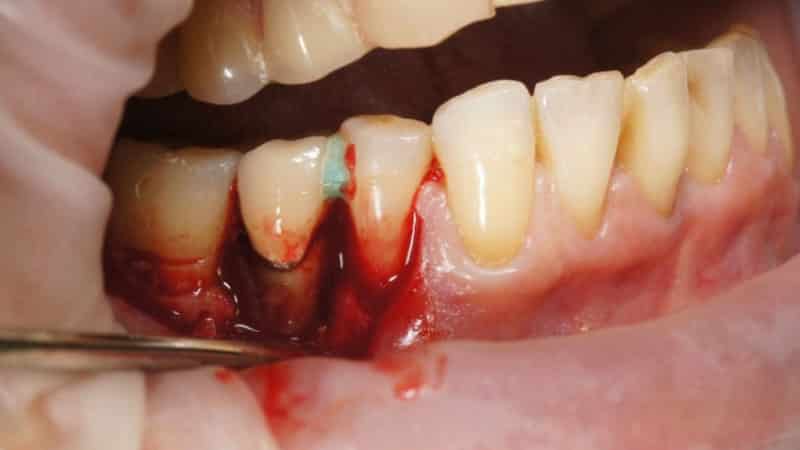

Открытая процедура включает в себя отслоение слизистой ткани десен хирургом-пародонтологом. Для этого врач делает небольшие разрезы в области шейки зубов. Полученные лоскуты отводятся от кости, обнажая зубные корни и участки разрушенной кости. На этом этапе врач получает полный доступ к поддесневым камням и налету, а также грануляционной ткани. Он удаляет эти патологические образования (включая карманы) с помощью хирургических кюрет. В современных клиниках также используется ультразвуковой скалер для выскабливания заместительной ткани и камней. Таким же образом может быть удален пародонтальный карман.

После этого врач проводит антисептическую обработку области. После удаления грануляционной ткани в костной ткани остаются пустоты. Дантист заполняет их костью, полученной синтетическим путем.

Заключительным этапом является наложение швов в области межзубных сосочков. Также на эту зону накладывается специальная повязка, защищающая рану от инфекции и способствующая регенерации ткани. Швы удаляются врачом через 10 дней.